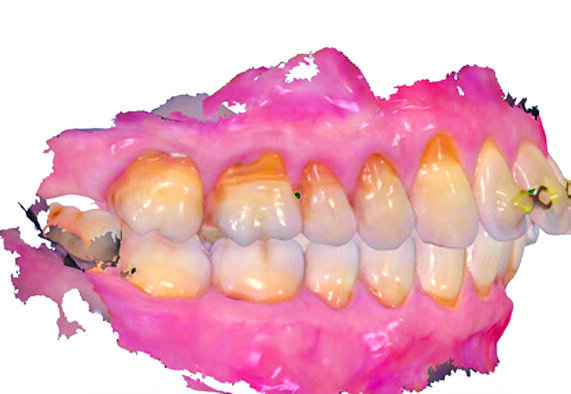

U prikazanom slučaju radi ilustracije su prije i poslije implantacije snimljeni intraoralni skenovi s pomoću skenera TRIOS (3Shape) (Slika 13.a i b14). Usporedbom prije i poslije prepoznaje se jedva promijenjen tijek mekog tkiva, a time je postignut estetski i prirodan krajnji rezultat. Aksijalni nagib prednjih zubi također je usklađen. Predstavljena metoda povećava predvidljivost estetskog ishoda, međutim, krije neke teškoće: kod dugačkog korijena, ograničena duljina rotirajućeg dijamantnog svrdla uzrokuje probleme u preparaciji fragmenta vestibularnog korijena. Roe i sur. to zaobilaze tako da vestibularno u razini vrha korijena fenestracijom prikažu to područje17. Budući da je za to potrebno odići mukoperiostalni režanj zbog čega je šav neizbježan, dolazi do stvaranja vestibularnog ožiljka17. Procedura ima smisla ako se umjesto toga ne može izvesti preparacija korijenskog fragmenta, a time i socket shield tehnika. Općenito bi terapeut trebao postupiti minimalno invazivno.

Slika 13.a i b: Usporedba profila mekog tkiva prije (gore) i poslije (ispod) implantacije s pomoću intraoralnog skena

Slika 14. Usporedba tijeka gingive prije (gore) i poslije (dolje) implantacije s pomoću intraoralnog skena